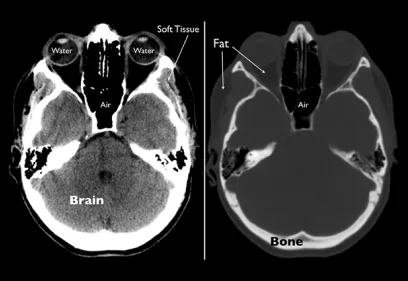

Cover image of a body scan of IMAGES magazine

IMAGES

Images is an annual publication on milestones and progress in radiology.

Read the latest issue